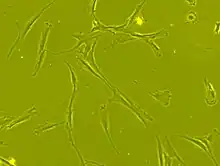

Human bone marrow derived Mesenchymal stem cell showing fibroblast-like morphology seen under phase contrast microscope (carl zeiss axiovert 40 CFL) at 63 x magnification

An example of human mesenchymal stem cells imaged with a live cell imaging microscope

The cell body contains a large, round nucleus with a prominent nucleolus, which is surrounded by finely dispersed chromatin particles, giving the nucleus a clear appearance. The remainder of the cell body contains a small amount of Golgi apparatus, rough endoplasmic reticulum, mitochondria, and polyribosomes. The cells, which are long and thin, are widely dispersed, and the adjacent extracellular matrix is populated by a few reticular fibrils, but is devoid of the other types of collagen fibrils.[11][12] These distinctive morphological features of mesenchymal stem cells can be visualized label-free using live cell imaging.